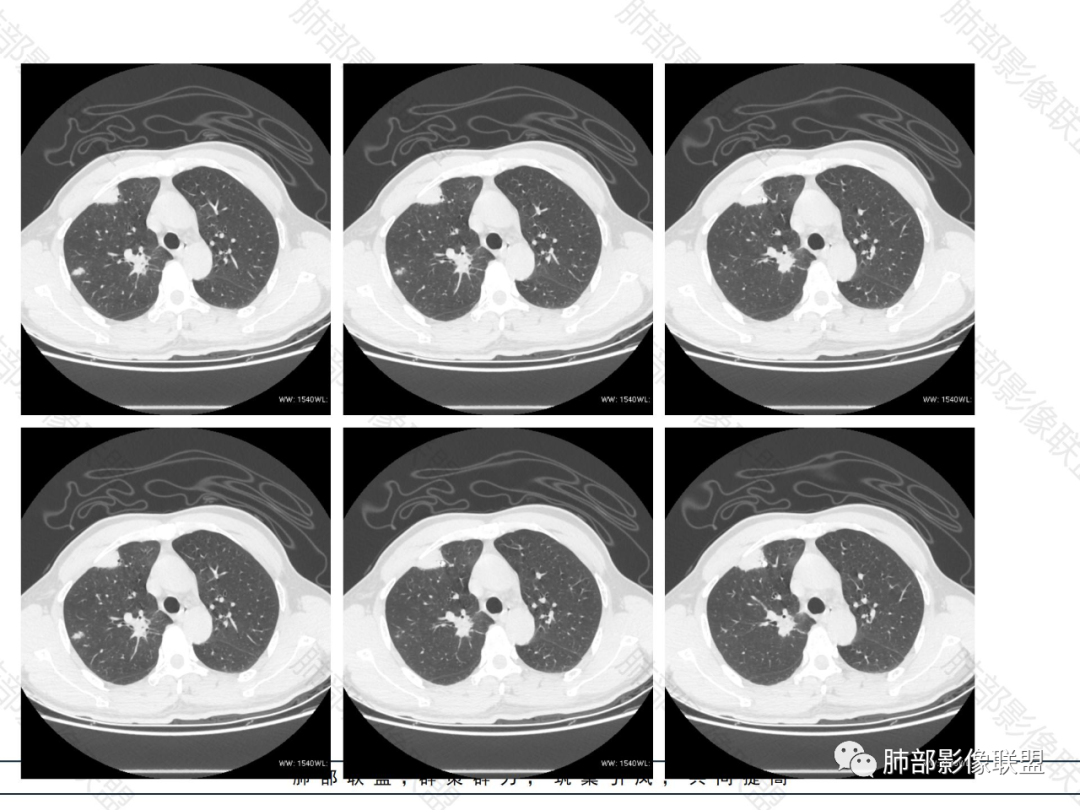

双肺多发大小不等结节,以胸膜下为主,部分边缘平直,彭隆,整体较密实,临床无症状体检发现,考虑淋巴瘤,转移瘤,IMT.

老年男性,发现占位半年,双肺多发结节,病灶边界清晰,浅分叶,部分支气管进入后堵塞,部分病灶内部密实,无增强,考虑真菌感染,淋巴瘤待排除。

双肺多发结节肿块,部分位于胸膜下,部分结节内可见扩张支气管,右肺上叶近肺门处结节呈分叶毛刺,支气管阻塞、扭曲扩张,考虑1淋巴瘤2腺癌转移。

双肺多发结节,密度均匀,部分可见支气管进去后堵塞,有胃部手术史,考虑淋巴瘤?鉴别腺癌转移,其他?

脾大表现,两肺叶多发结节,部分呈肿块(浅分叶轮廊),实性密度,边缘清楚,有膨隆,近胸膜下分布,支气管僵直略扩张,一元论,首选淋巴瘤。

双肺多发结节肿块,胸膜下支气管树旁为主,部分内可见支气管穿行,支气管扩张。淋巴瘤?肉芽肿性多血管炎?鉴别转移

必有路:老年男性,两肺多发结节,团块,病灶都位于胸膜下,血管相关,有支气管充气征,分叶,无坏死,周围无晕疾病谱:隐球菌病,GPA,OP,malt,转移,IgG4相关,栓塞诊断:鉴于患者体检发现半年,症状逍遥重点考虑 淋巴瘤 可能鉴别:隐球菌病,GPA,IgG4相关,转移

多发团块影,胸膜下为主,边缘清楚、膨隆、平直,部分病灶可见分叶,病灶内支气管穿行,血管穿行,考虑淋巴瘤。

刚看了视频,老年男性,体检发现,30年前有胃部手术史。双肺野多发结节肿块影,沿支气管血管束或胸膜下分布,有的结节内似有小空洞,支气管进入走形自然,肿块边缘膨隆,有分叶,支气管进入后有的截断,大部分支气管穿过,走形自然,纵隔内未见明显肿大淋巴结,总体考虑淋巴瘤,炎性肉芽肿(肉芽肿血管炎或隐球菌肺炎)等。考虑后者可能性大,肉芽肿血管炎或隐球菌肺炎,鉴别淋巴瘤。

病变分布特点,胸膜下,叶间胸膜下为主,呈大小不等结节级团块影,部分病灶内见支气管影,病灶收缩不明显,从分布及慢性发病看,隐球和淋巴瘤都可,补充增强,病灶内见血管穿行,强化不明显,支持淋巴瘤

老年男性,两肺多发结节肿块,胸膜下分布为主,部分支气管进入闭塞,增强扫描有强化,血管穿行无破坏,边缘尚光滑,周围无晕,病灶整体膨隆为主,半年病程,症状逍遥,首先考虑淋巴瘤

棉花糖:双肺多大小不等结节,边缘清楚,无毛刺,浅分叶,胸膜下分布为主,内可见支气管穿行,增强后中等程度强化,病灶内血管走行自然,考虑淋巴瘤,鉴别GPA